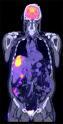

September 15, 2009 - Positron Corp. announced that the Ministry of Health and Long Term Care of Ontario, Canada is making positron emission tomography (PET) scanning a publicly insured health service available to cancer and cardiac patients under conditions where PET scans have been proven to be clinically effective. The Ministry of Health and Long Term Care (MOHLTC) has adopted an evidence-based approach to the introduction of PET imaging in the province for certain cancer and cardiac indications.